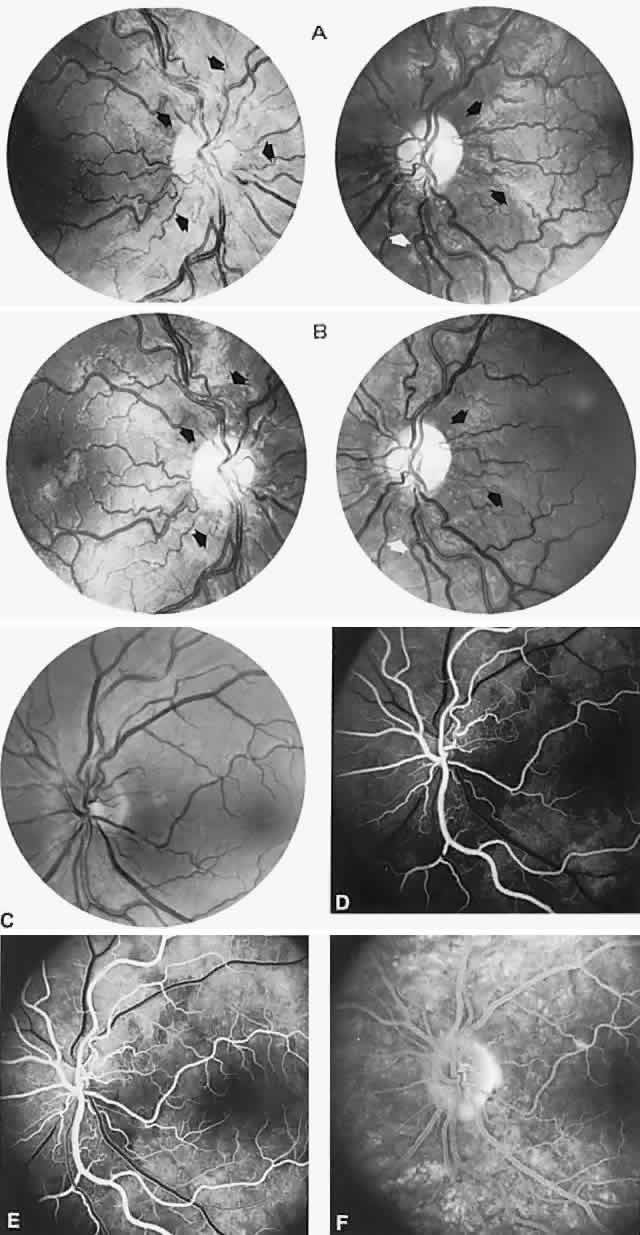

angiographic studies. Arch Ophthalmol 102:981, 1984 90. Newman NJ: Leber's hereditery optic neuropathy: new genetic considerations. Arch Neurol 50:540, 1993 91. Newman NJ, Lott MT, Wallace DC: The clinical characteristics of pedigrees of Lebers' hereditary optic neuropathy

causing intracranial hypertension without ventriculomegaly. Arch Neurol 48:740, 1991 180. Katz B: The dyschromatopsia of optic neuritis. Trans Am Ophthalmol Soc 93:685, 1995 181. Mojon DS, Rösler KM, Oetliker H: A bedside test to determine motion stereopsis using the Pulfrich phenomenon. Ophthalmol 105:1337, 1998 182. Selhorst JB, Saul RF: Uhthoff and his symptom. J Neuroophthalmol 15:63, 1995 183. Keltner JL, Johnson CA, Spurr JO et al: Visual field profile of optic neuritis: one-year follow-up in the optic